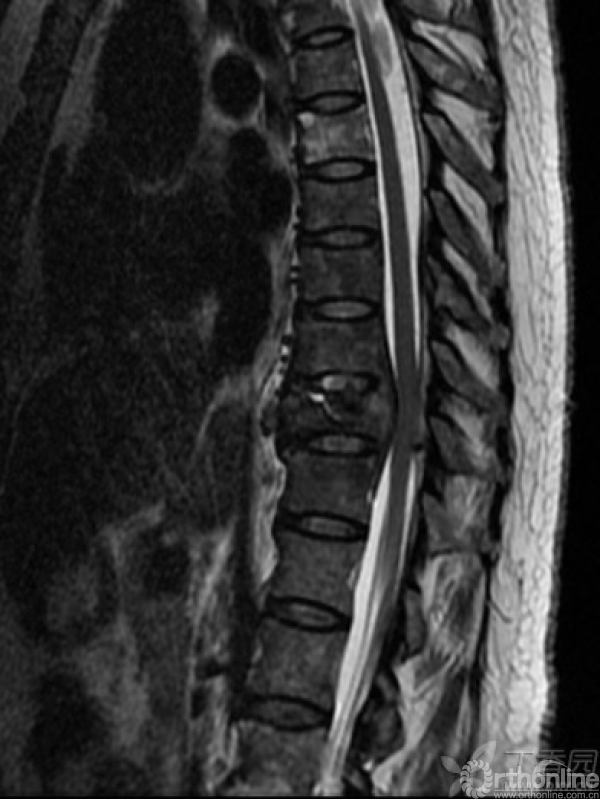

胸椎多椎体病变,如果诊断和治疗?